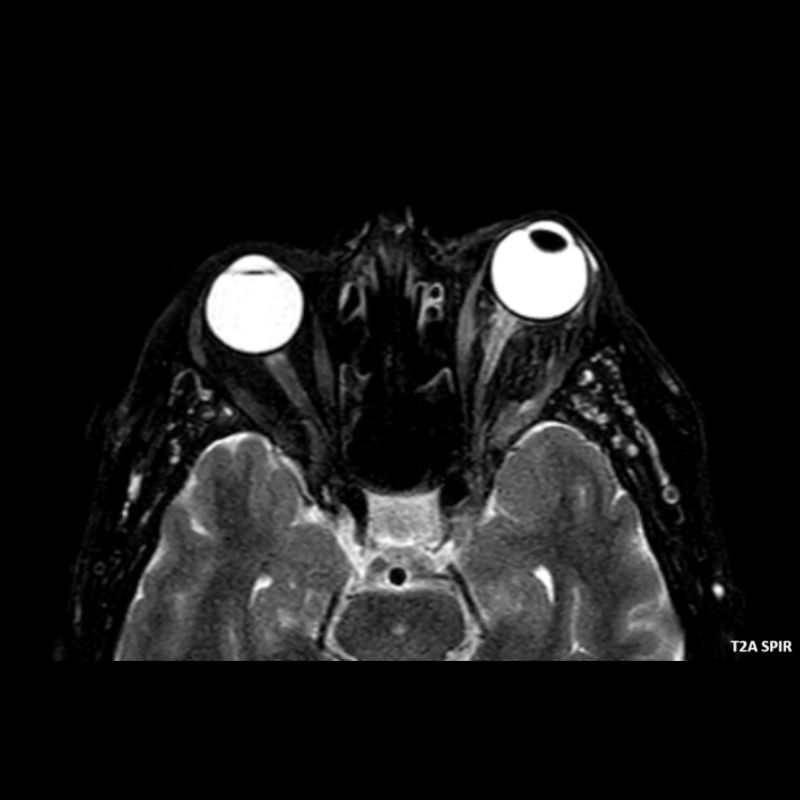

- A) Orbital MRG’de yağ baskılı T2A görüntülerde sol orbital globta ekzoftalmus (ok) izlenmiş olup retrobulbar yağlı dokuda kirlenmeler (ok) ve dilate superior oftalmik ven (ok) dikkati çekiyor. Beyin MRG’de kontrastlı T1A görüntüde sol kavernöz sinüste simetriğine oranla genişleme (ok) izleniyor.

- BT ve MRG: Propitozis, ekstraokuler kaslarda genişleme, superior oftalmik vende genişleme ve tortiyozite, ipsilateral kavernöz sinüste genişleme gösterilebilir. Serebral venöz konjesyonu olan ve intrakraniyal basınçları yükselen hastalarda serebral ödem, hemoraji, leptomeningeal ve kortikal venlerin dilastasyonunu görülebilir. Bunlara ek olarak travmaya sekonder olgularda BT ile eşlik eden fraktürler gösterilebilir.